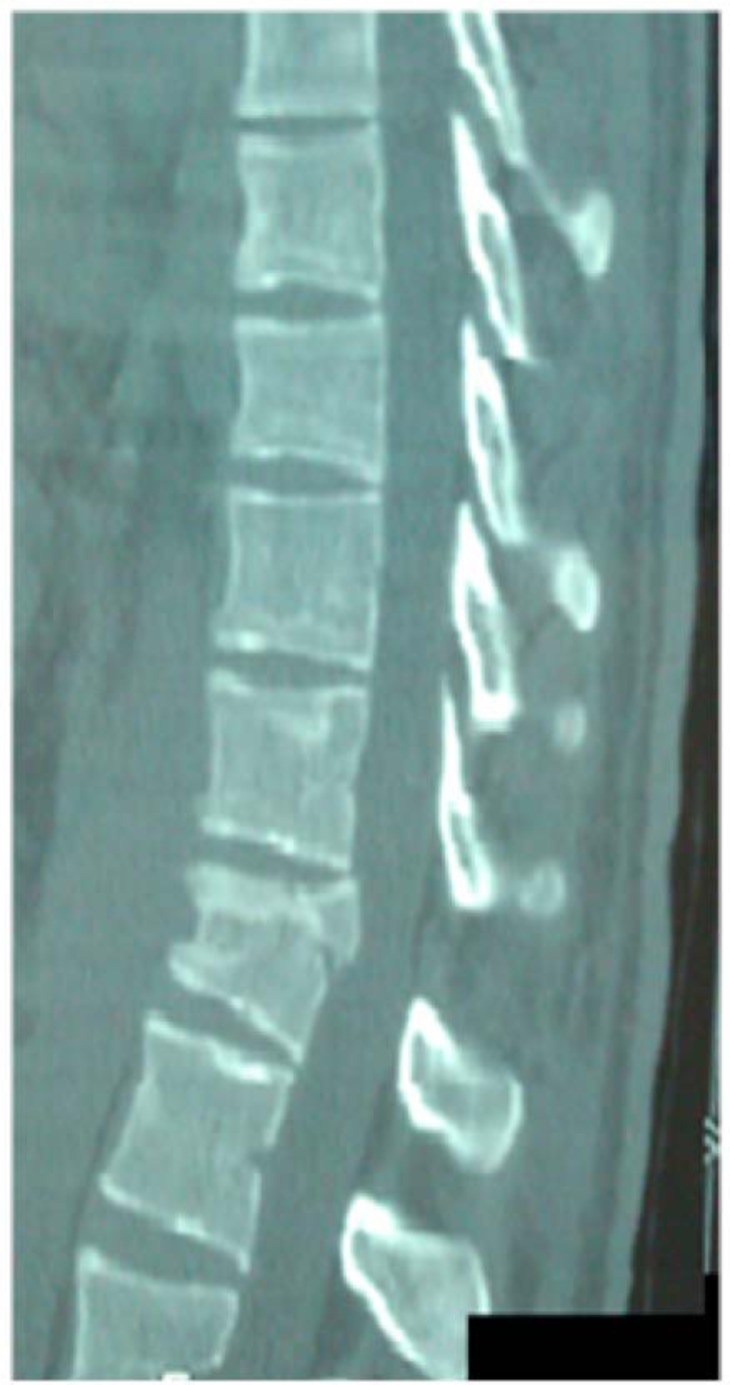

Upon admission, palpation revealed tenderness at the thoracolumbar region. His neurologic examination was normal with no motor or sensory deficit of the lower and upper limbs. Ultrasonography was performed to exclude blunt abdominal concomitant injuries. Simple radiographic evaluation of the cervical spine, thorax and pelvis did not demonstrate associated injuries. Radiographs (Figs. 1, 2) and CT scans (Fig. 3) of the thoracolumbar spine revealed a transverse fracture at the level of T12. The CT scan further demonstrated a split of the posterior elements, progressing anteriorly into the vertebral body. Conservative treatment was decided and the patient, following an initial period of bed rest, was mobilized wearing a thoracolumbar orthosis. Appropriate antithrombotic prophylaxis with low molecular weight heparin was administered, until full ambulation was achieved. The patient was followed up with serial thoracolumbar radiographs for the first 6 weeks of ambulation and later on, in one month intervals. The thoracolumbar orthosis was applied for three months. At the 5th month follow-up, he was pain free with radiographic signs of mild vertebral kyphosis. Upon completion of treatment, he returned successfully to pre-injury levels of daily activity, without any impairment.

Fig. (1). Lateral radiograph demonstrating a T12 transverse fracture.

Fig. (3). CT scan – sagittal plane, demonstrating the same T12 fracture shown in the radiographs.